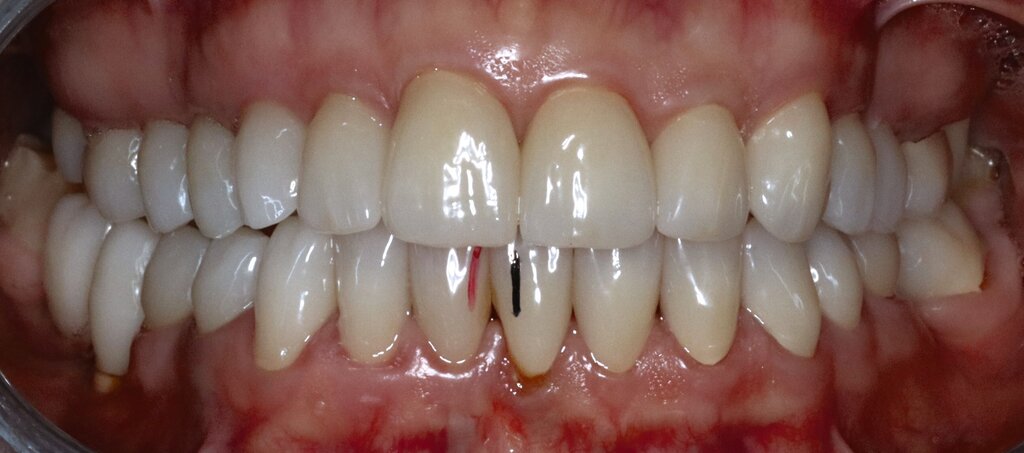

Eine 62-jährige Patientin stellte sich im Jahr 2025 in der CMD-Sprechstunde vor. Gemäß der allgemeinen Anamnese bestanden keine Vorerkrankungen. Die spezielle Anamnese zeigte den Zustand nach alio loco erfolgter prothetischer Rekonstruktion im Dezember 2024 mit festsitzendem Zahnersatz. Die Versorgung umfasste 14 Kronenrestaurationen (17–27) im Oberkiefer sowie zwölf Kronen (45–36) und zwei Implantatsuprakonstruktionen (046, 047) im Unterkiefer.

Die Patientin schilderte eine deutliche Instabilität des Zusammenbisses mit punktuellem Kontakt auf der linken und fehlenden Zahnkontakten auf der rechten Seite seit dem Tag der Insertion des Zahnersatzes. Ein annähernd stabiler Zahnkontakt sei nur durch aktiven Verschub des Unterkiefers nach rechts im Sinne eines Eingleitens in die Interkuspidation des Zahnersatzes erreichbar. Bei Provokation dieser „schiefen“ Unterkieferposition komme es jedoch aufgrund der muskulären Anstrengung nach kurzer Zeit zu Beschwerden. Die Patientin gab in diesem Zusammenhang Schmerzen und eine Grundanspannung der Kau-/Nackenmuskulatur und Kopfschmerzen an, jeweils links > rechts (Abbildung 4).